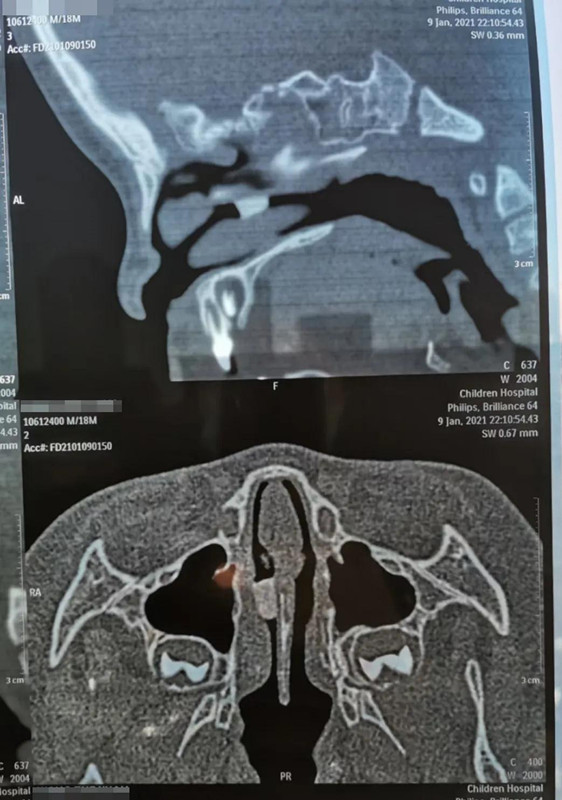

1月9日晚10点多,在夜深人安睡的时候,18个月男宝帅帅(化名)哭闹着被妈妈抱进a片网站 就诊。妈妈说,晚上5点多,帅帅打碎了瓷鸭子玩具,偷偷把瓷鸭子嘴塞进鼻子里。经鼻腔三维CT重建,发现异物在右侧鼻腔较深位置,需次日全麻下手术取出。

取出8mm长异物